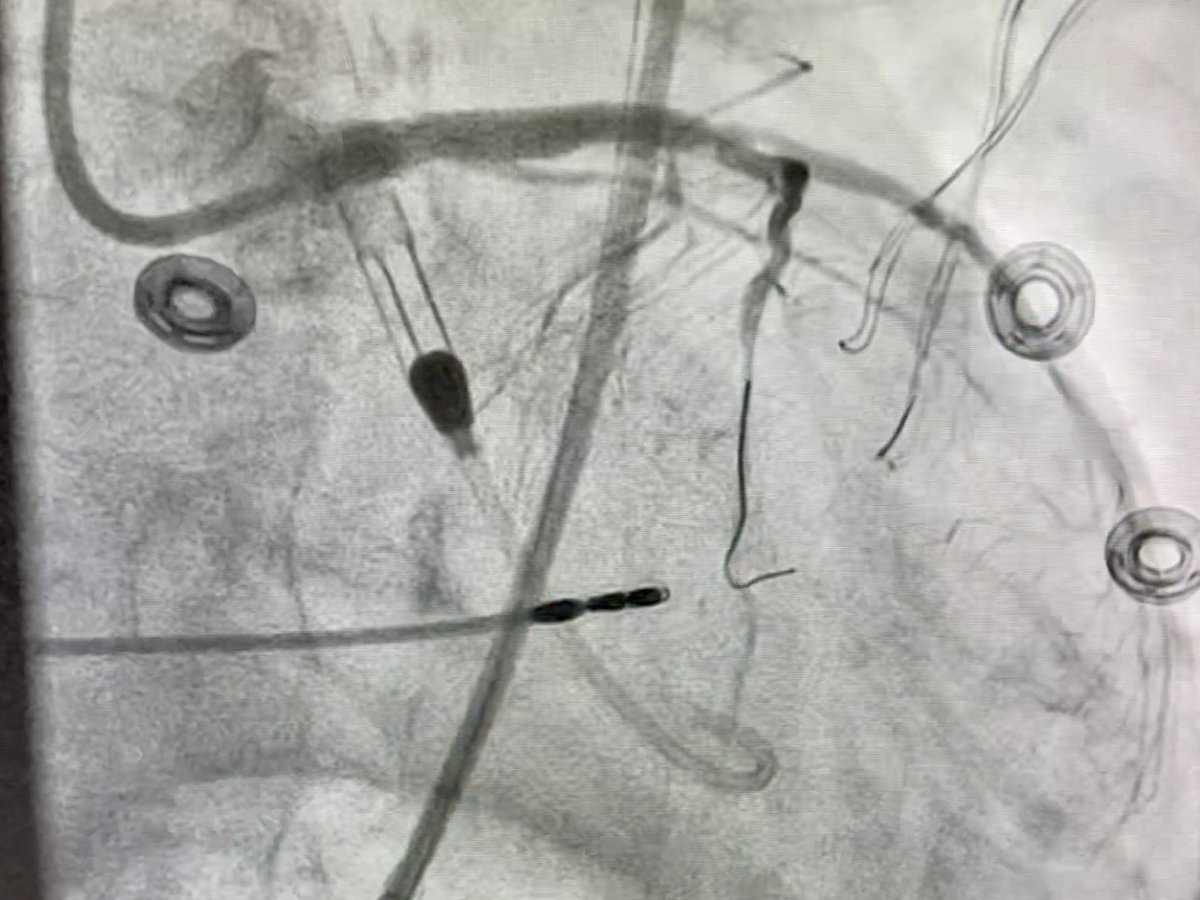

62 y/o male presents with NSTEMI. Boarded for cath in am. Prior to cath VT arrest and on vasopressors Findings at cath, severe LAD, CTO LCx, CTO RCA. LVEDP 34mmhg, EF 10%. Severe PAD. Rx with IC fellow sticks #PercAx Impella and IVUS guided revasc. Now off vasopressors.

DrAmirKaki's tweet image. 62 y/o male presents with NSTEMI.  Boarded for cath in am.  Prior to cath VT arrest and on vasopressors Findings at cath, severe LAD, CTO LCx, CTO RCA.  LVEDP 34mmhg, EF 10%.  Severe PAD.  Rx with IC fellow sticks #PercAx Impella and IVUS guided revasc.  Now off vasopressors.